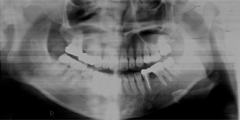

口内写真とパノラマレントゲンを撮影し、まずは顎の骨の状態まで詳しく確認しました。

写真(1)

院長の吉本の診断は以下でした

・歯がない期間が長く続いたため隣の歯が横に倒れてしまい、歯と歯との間に隙間が2ケ所できてしまっていた。